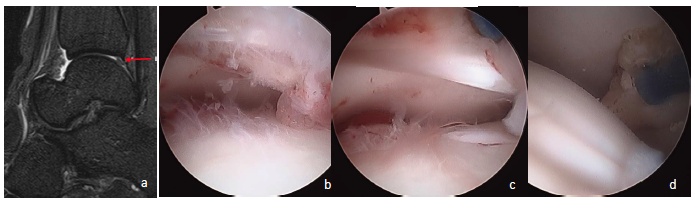

Once I am in the posterior space I can inspect the ankle laterally and centrally. Simply dorsiflexing the ankle widens the space. By switching the scope to the medial portal, you can inspect the medial joint and easily visualize the deep deltoid ligament. Just like one would do with the anterior ankle, surgeons can divide the joint into medial, central and lateral quadrants (see fourth photo set above). Once the surgeon is done with the ankle joint, proceed inferiorly to inspect the posterior talar process/os trigonum and, if necessary, the posterior facet (see fifth photo set above).